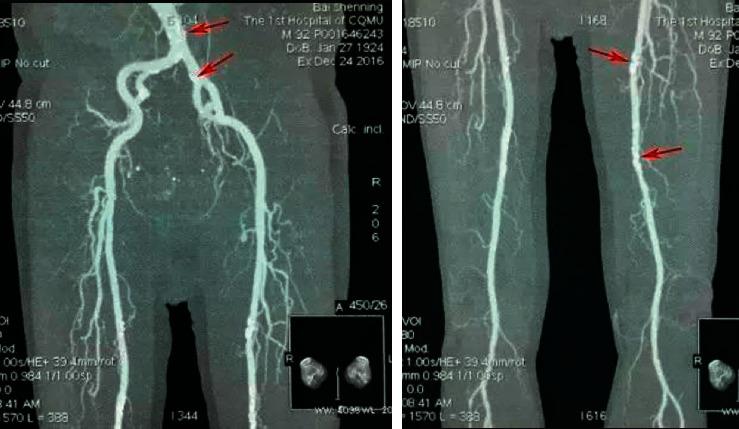

The thrombosis process is a multifactorial evolution process that includes many genetic and environmental factors that interact with each other. It refers to the existence of blood deposits in the heart or blood vessel walls or abnormal blood clots in the circulatory blood flow during the survival period of humans or animals for some reason. This article aims to analyze the research of blood vessel stenosis caused by arterial thrombosis of the lower extremities under the diagnosis of cardiac ultrasound based on the mobile information system. This article first introduces the mobile information nursing system and its development process. The mobile nursing information system has experienced three stages of development and is an important application of the further development of science and technology in medical information technology. It also proposes a medical diagnosis method based on SRM on a mobile platform and gives a technical roadmap for heart sound analysis and processing. Then, based on the mobile information system, the formation of arterial thrombosis in the lower extremities was analyzed and discussed in the ultrasound diagnosis of the heart, and the vascular stenosis caused by the arterial thrombosis of the lower extremities was analyzed by imaging. Experimental results show that when there is >50% stenosis or complete occlusion, the CTA false positive is more prominent, especially when the calf artery type is complete stenosis. The main cause is that the circulation of the lower limbs is very poor, the blood entering the blood vessels of the lower limbs is scarce, the capillaries are weakly enhanced, and the quality cannot be improved.